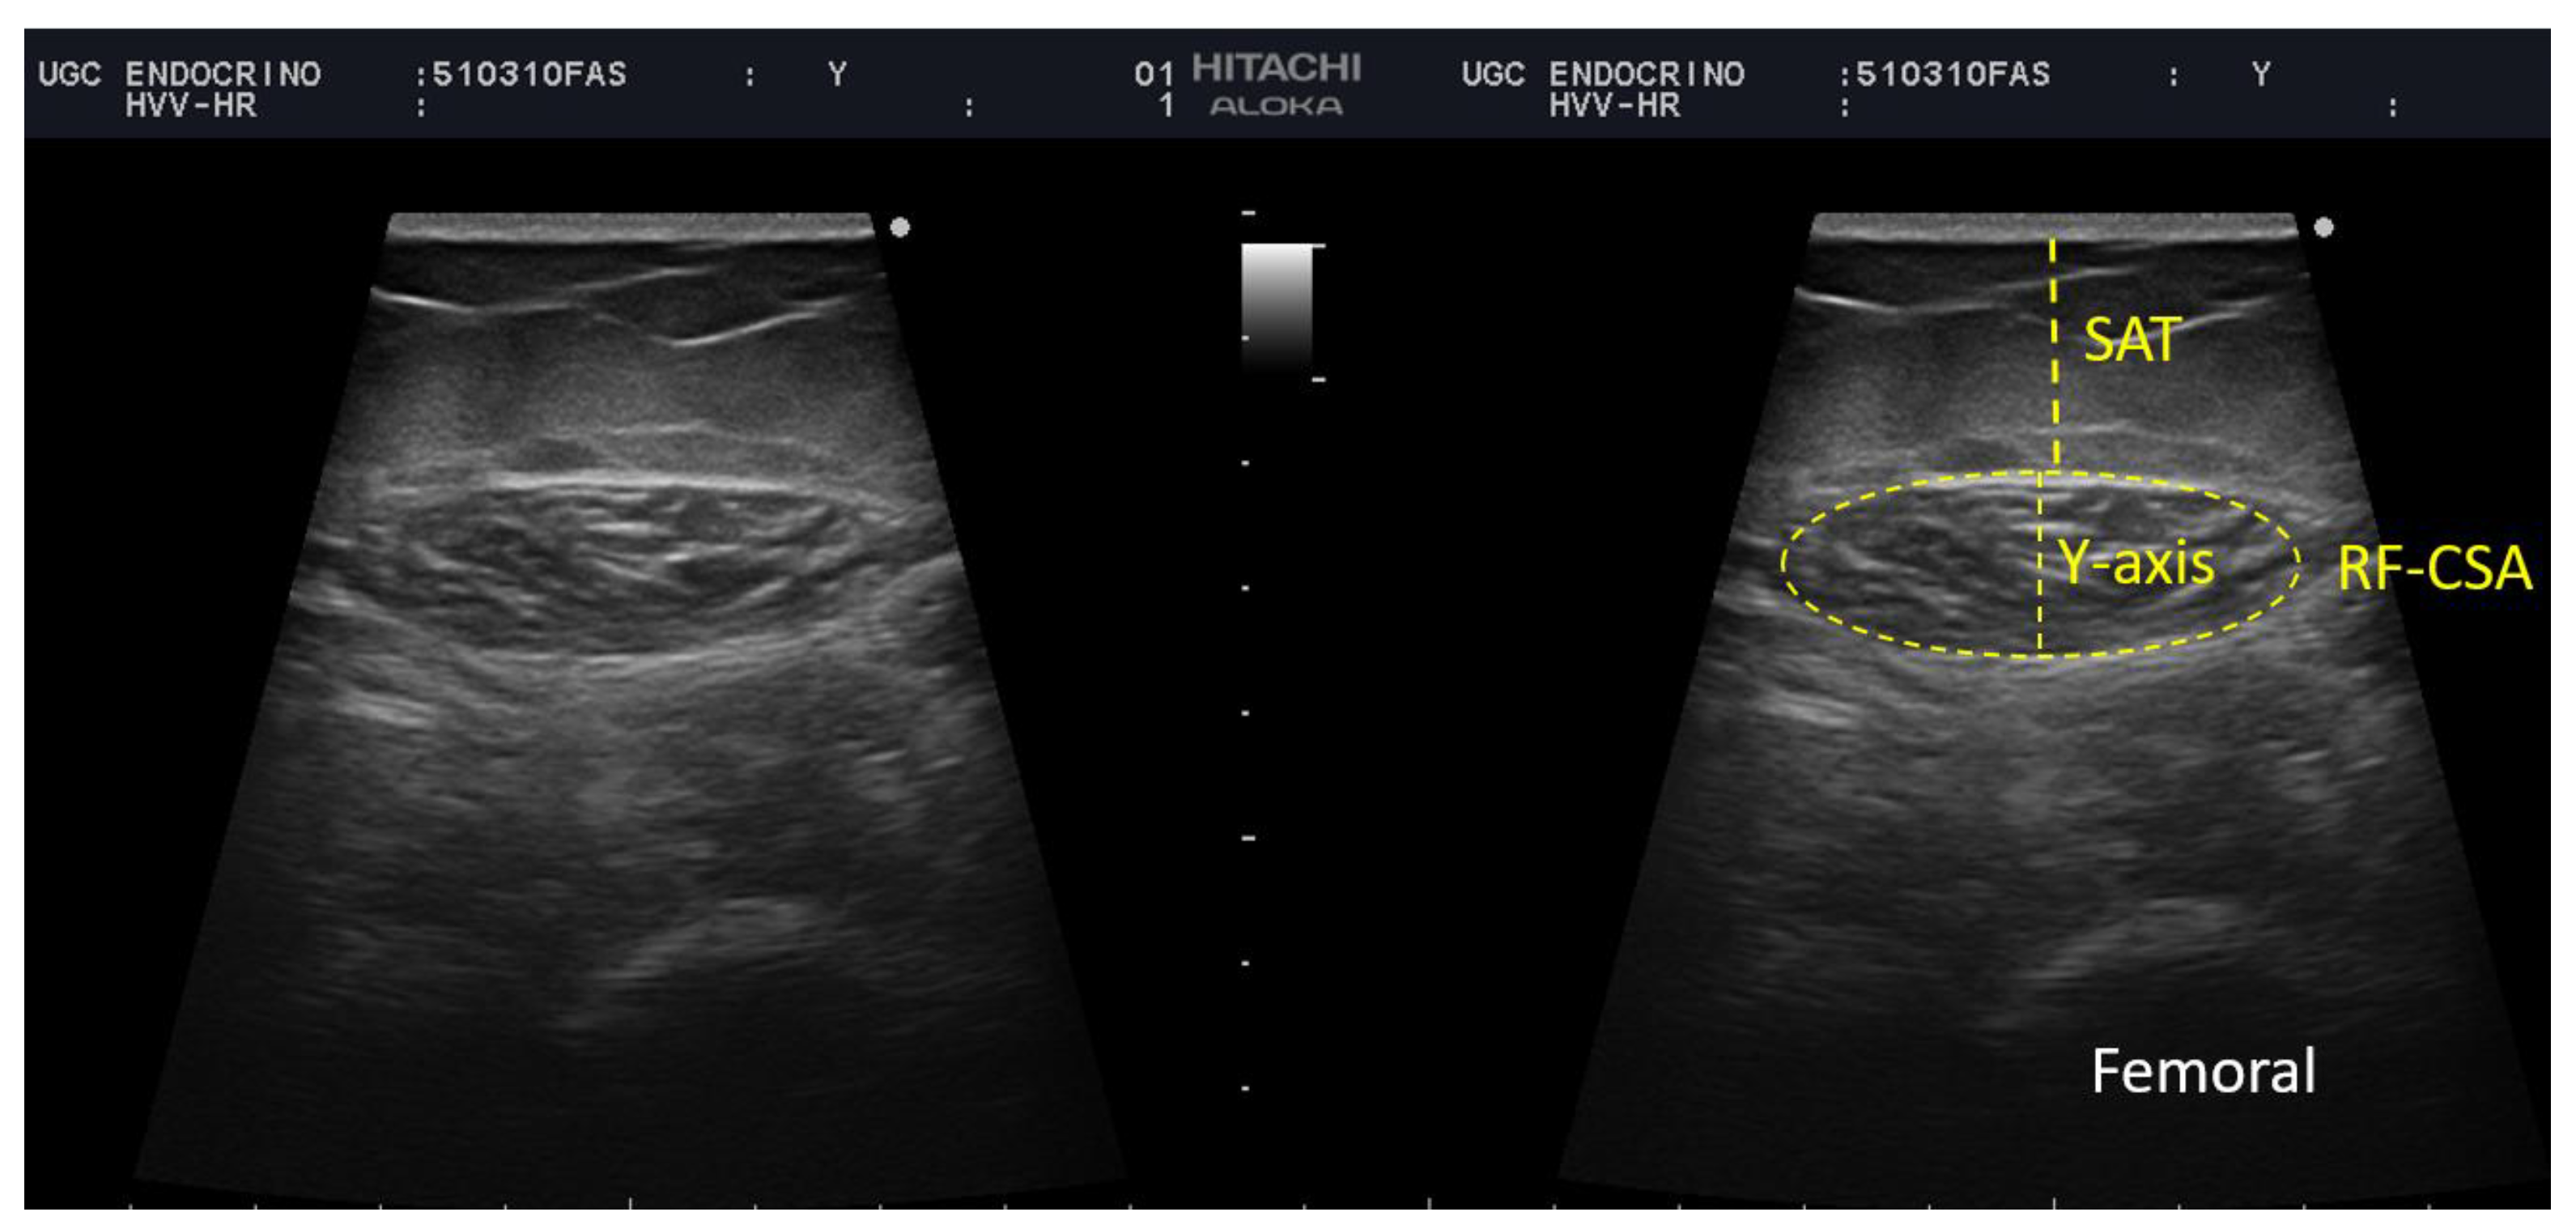

Rectus Femoris (RF) Ultrasound Assessment

| Muscle thickness (Y-axis) | 1.38 (1.15–1.61) | 1.40 (1.15–1.63) | 1.22 (0.87–1.60) | 0.564 | |

| X-axis | 3.95 (3.35–4.24) | 3.99 (3.66–4.24) | 3.28 (2.69–4.48) | 0.266 | |

| Cross-sectional area (cm2) | 4.35 (3.5–5.33) | 4.76 (3.56–5.43) | 3.65 (2.80–3.89) | 0.025 | |

| Muscle circumference | 9.43 (8.53–10.15) | 9.54 (8.73–10.30) | 8.61 (7.55–9.83) | 0.096 | |